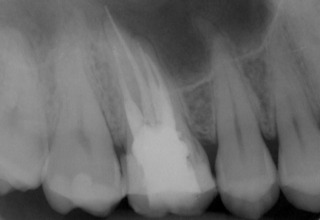

Nach erfolgter Information über die vermutete Prognose unternehmen wir den Versuch, das frakturierte Instrument darzustellen. Nach Entfernung der Aufbaufüllung werden die Kanaleingänge dargestellt (Abb. 2). Es zeigt sich, dass neben dem distovestibulären Kanal auch ein vierter Kanal (mb2) vorhanden ist. Die Darstellung der Wurzelkanaleingänge erfolgt in unserem Haus mit dem Aufsatz 1R des Tigon+. Dank der Abwinkelung des Instruments profitiert man von einer sehr guten Sicht auf die Behandlungsstelle. Zudem erlaubt es ein schnelles und gezieltes Abtragen von Dentin, ohne dabei den Zahn unnötig zu schwächen.

Abb. 2: Darstellung aller Wurzelkanaleingänge. Die palatinale Wurzelfüllung wird belassen, da sie für gut befunden wird.

Nach Darstellung aller Wurzelkanaleingänge wird in einem zweiten Schritt das frakturierte Wurzelkanalinstrument dargestellt (Abb. 3 u. 4). Hierfür verwenden wir den Aufsatz 3E des Tigon+. Durch die schmale und lange Form des Instruments erreichen wir einen tiefen und schmalen Zugang.

Abb. 3 u. 4: Zustand nach Revision des Wurzelkanals und Darstellung des frakturierten Instruments.